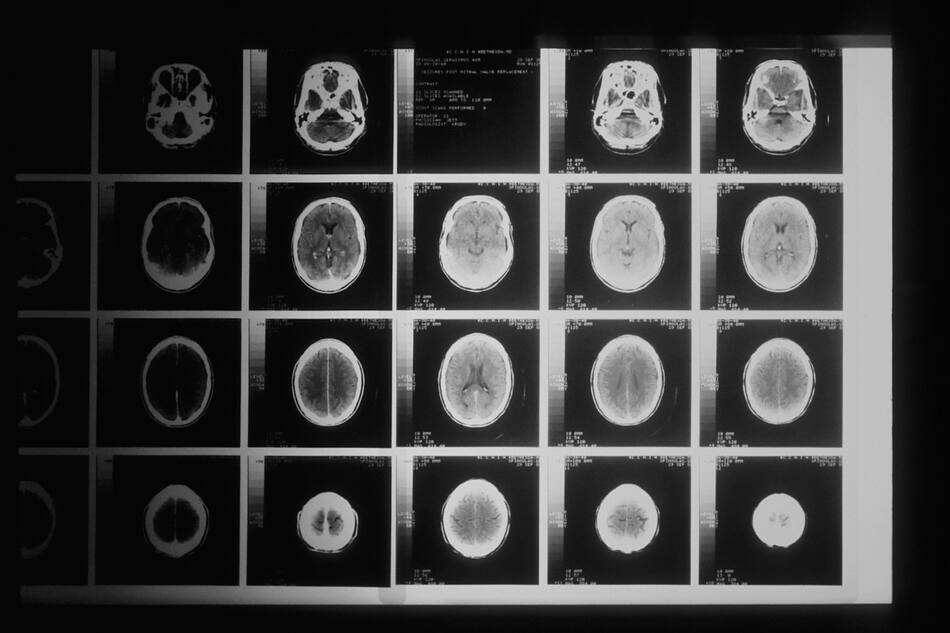

Médicos sacaron un gusano de un cerebro. Foto: Unsplash

Médicos extrajeron un gusano. Foto: @lanoticiasv

Luego de extraer el gusano, la paciente mejoró. Foto: Unsplash.